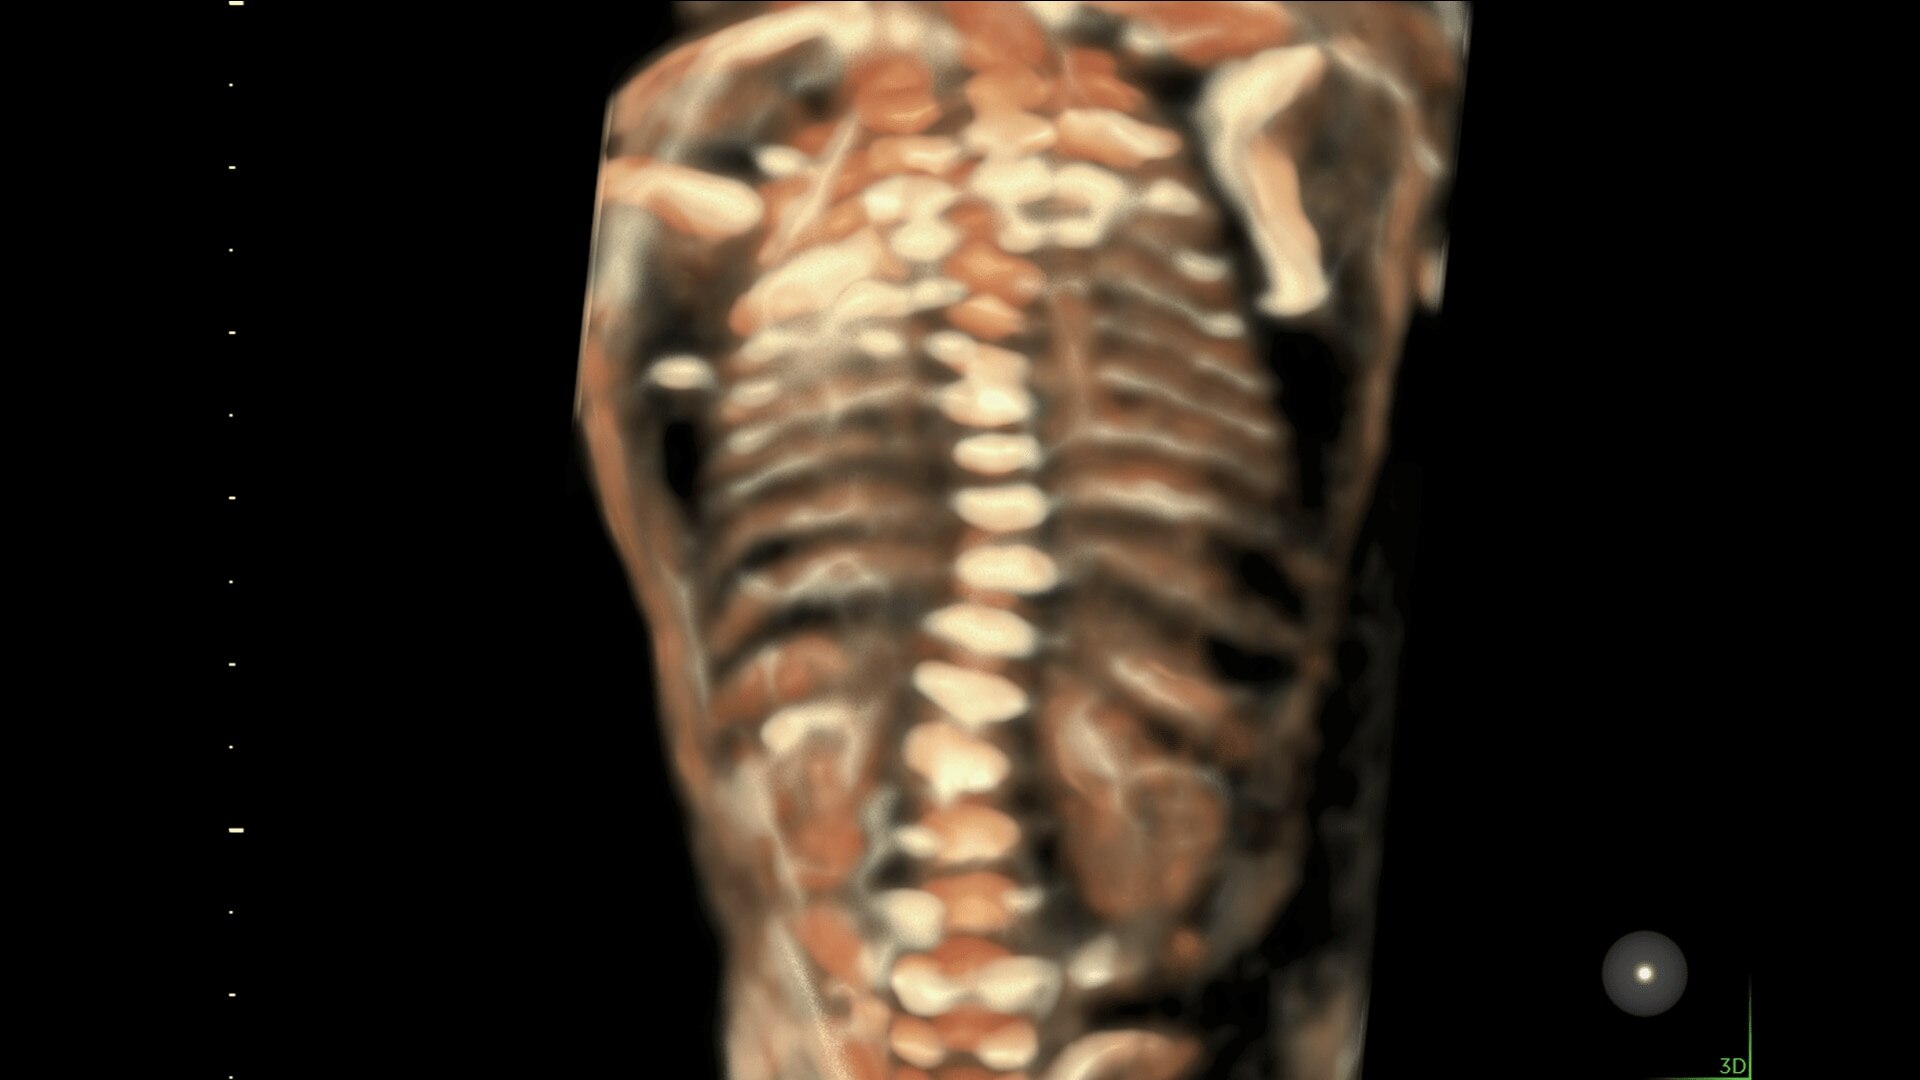

Enhanced Volume Imaging

Deliver next generation 3D/4D & Color images with HDlive Studio+